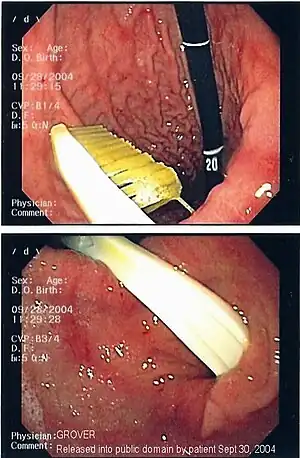

| A foreign body - in this case a swallowed toothbrush - located in the stomach cavity by using an endoscope. | |

Endoscopic foreign body retrieval is the first-line treatment for removal of a foreign body from the alimentary tract.[10]